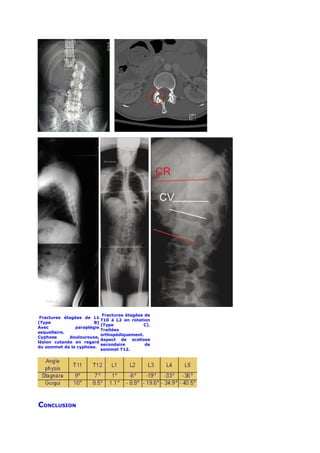

La déformation sagittale de la fracture se mesure par l’angle de cyphose

vertébral CV.

La déformation régionale prend en compte la déformation de la vertèbre

fracturée mais aussi la déformation engendrée par les éventuelles lésions

discales ou ligamentaires associées.

Cet angle de cyphose régional CR permet le calcul de l’angle régional

traumatique ART qui n’est que la soustraction de la déformation régionale CR

par l’angulation physiologique régionale du niveau vertébral fracturé.

ART             =             CR             mesurée              –

angulation physiologique